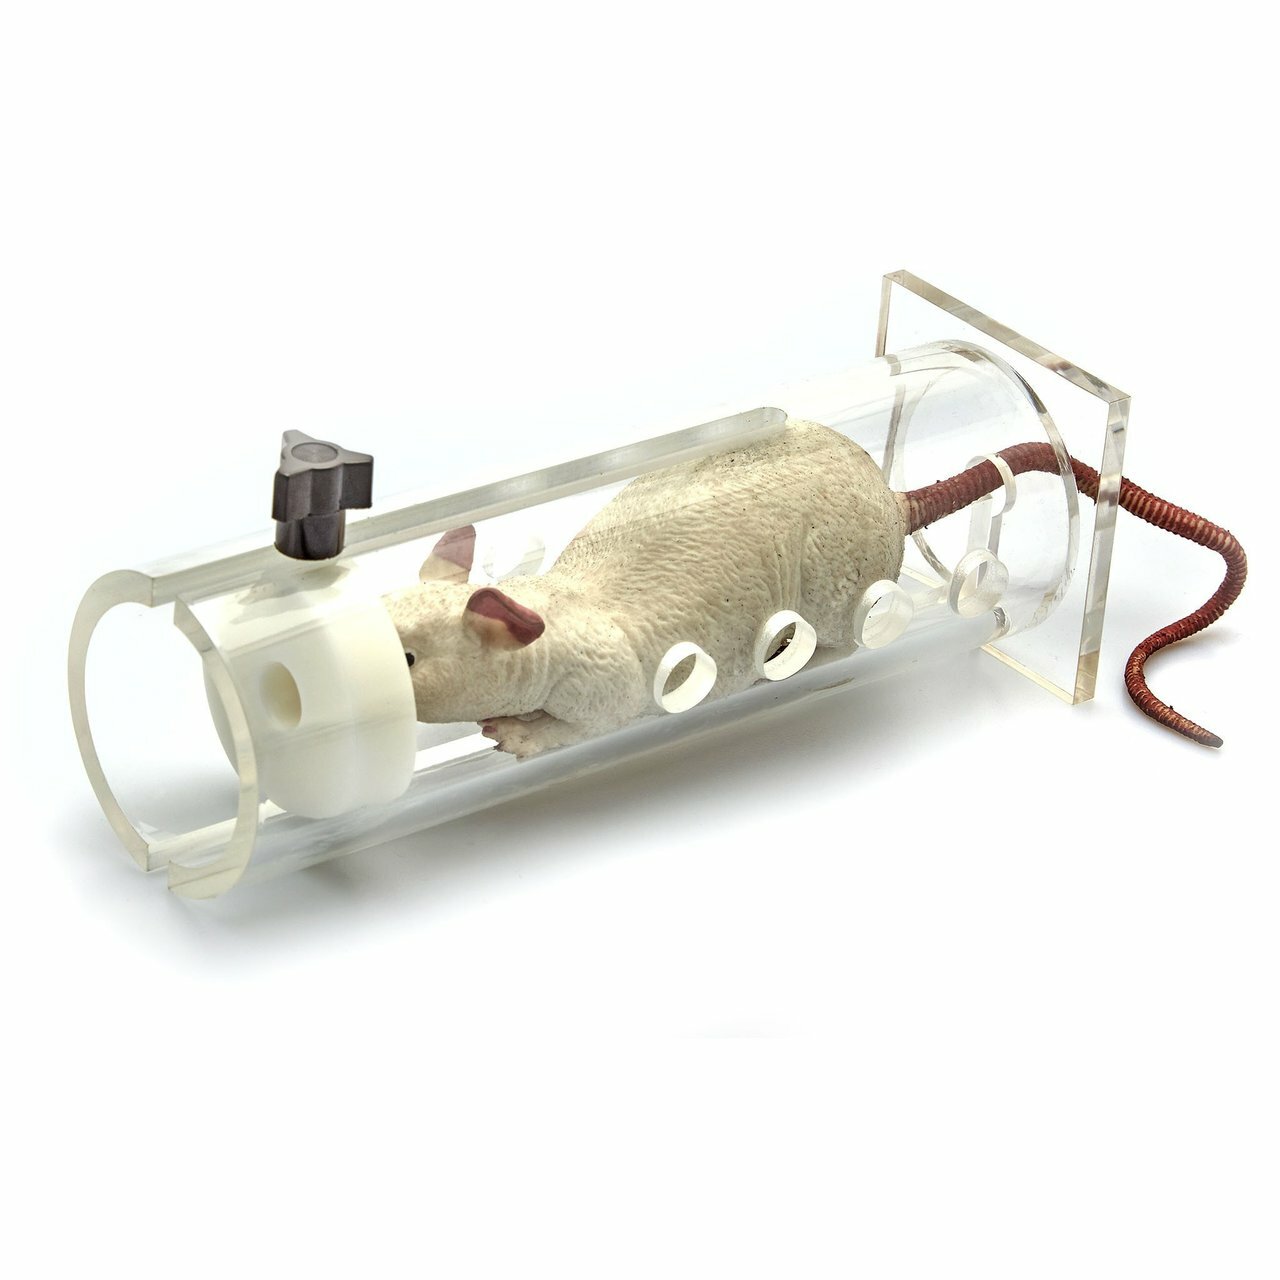

- Create and induce a variety of animal models

Achieving any accurate animal studies requires access to the suitable facilities for working with laboratory animals, proper maintenance and breeding in a place that fully complies with the standards of laboratory animal breeding and with advanced and up-to-date equipment and facilities. In this regard, Histogenotech Research Center, with many years of experience and experienced specialists, carries out extensive activities in order to comply with the principles of standard care and practice of laboratory animals.